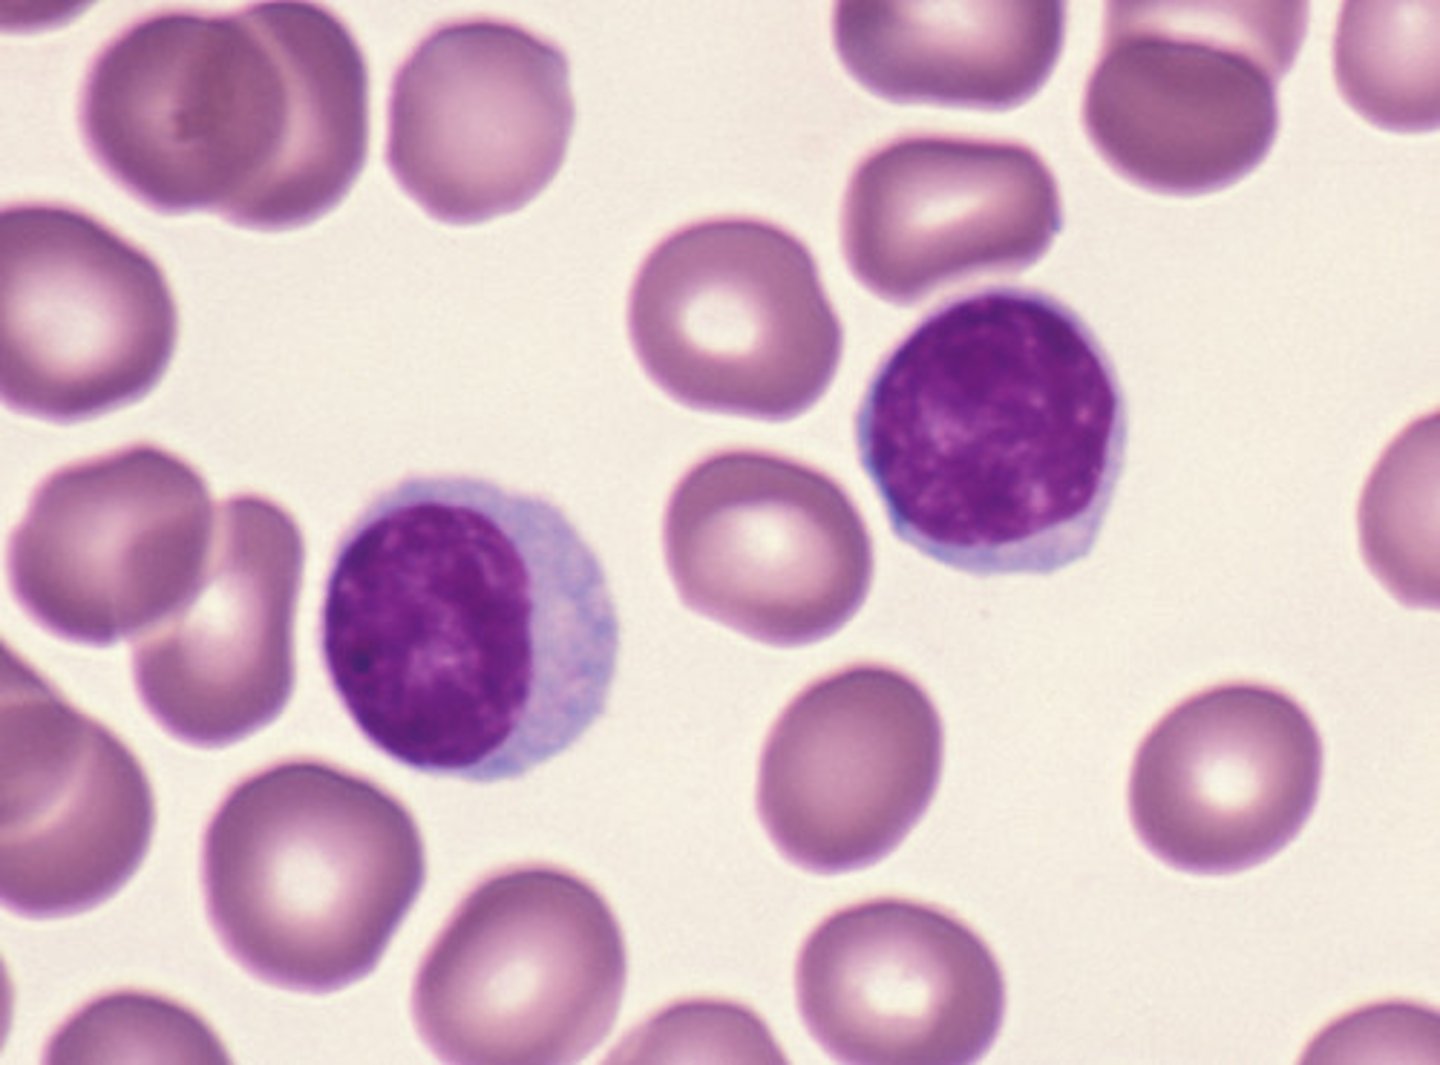

lymphocyte

MAMMAL

no granules

- dark purple nucleus, round to oval, takes up most of the cell

- small amount of cytoplasm